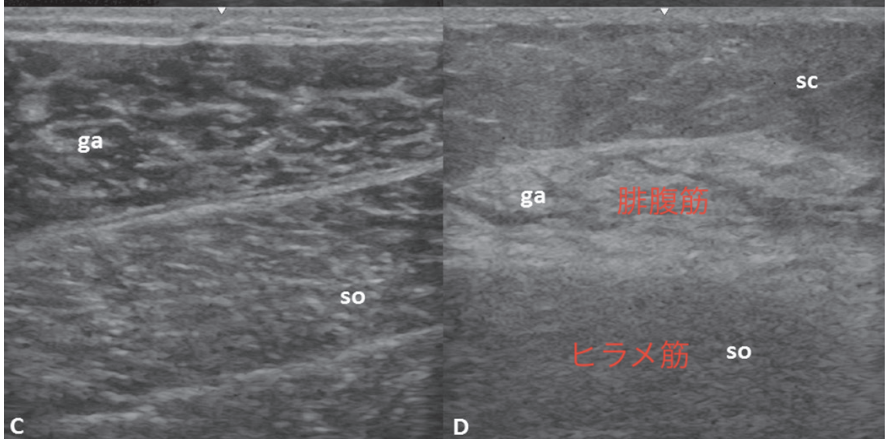

IBMでは前腕屈筋群、大腿四頭筋の萎縮が有名であるが、エコーでは深指屈筋と浅指屈筋のコントラスト、ヒラメ筋と腓腹筋のコントラストが有用と報告されている。

で、腓腹筋での輝度上昇が特徴とされる。